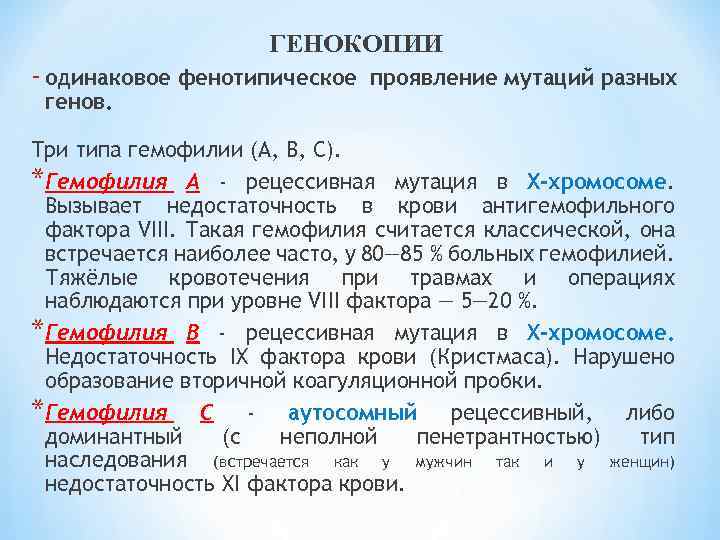

Генетика гемофилии: рецессивные гены и их проявления